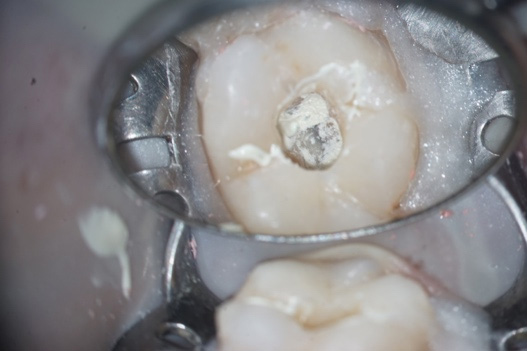

After anesthesia and absolute isolation, root canal desobturation was performed with the rotary file system (Figure 2A). For more effective disinfection, the irrigating substances (5.25% Sodium Hypochlorite and 17% EDTA) were activated ultrasonically (PUI). Based on the case history, we chose to perform it in two sessions, placing a calcium silicate-based dressing (Bio-C TEMP) (Figure 2B) and composite resin shielding between sessions. The patient was instructed to return within 15 days.

Figure 2: Placement of intracanal dressing (Bio-C Temp)